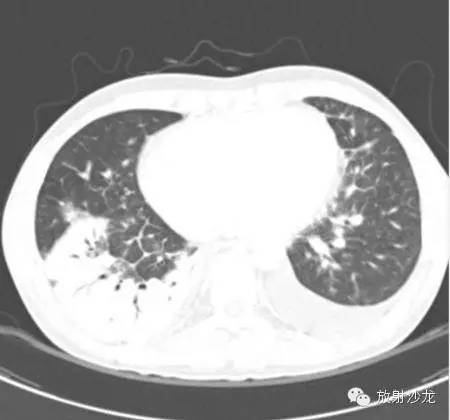

(第一次胸片示两肺中野及右肺下野多发斑片状高密度影。胸部CT示多发斑片状磨玻璃样密度增高影以及实变影,同时伴有小叶间隔的增厚。其中有些病灶部分表现为“铺路石征”。两周后CT随访显示这些病灶的密度和范围都增大。电视辅助胸腔镜肺活检下,活检标本病理诊断结果为急性纤维素性机化性肺炎。上述病变经高剂量糖皮质激素治疗三周后明显改善。)

大量急性纤维素性机化性肺炎的影像学显示已经累及双肺,并存在弥漫浸润性病变,双肺还表现出弥漫斑片状实变阴影改变,一般双侧肺底比较多见,部分患者出现单侧结节状实变阴影, 很容易将其与结核、肿瘤等混淆。急性纤维素性机化性肺炎组织学特征主要是肺泡腔内沉积大量纤维素,同时形成均质嗜酸性的纤维素球,少数患者的纤维球周边出现新的纤维组织。